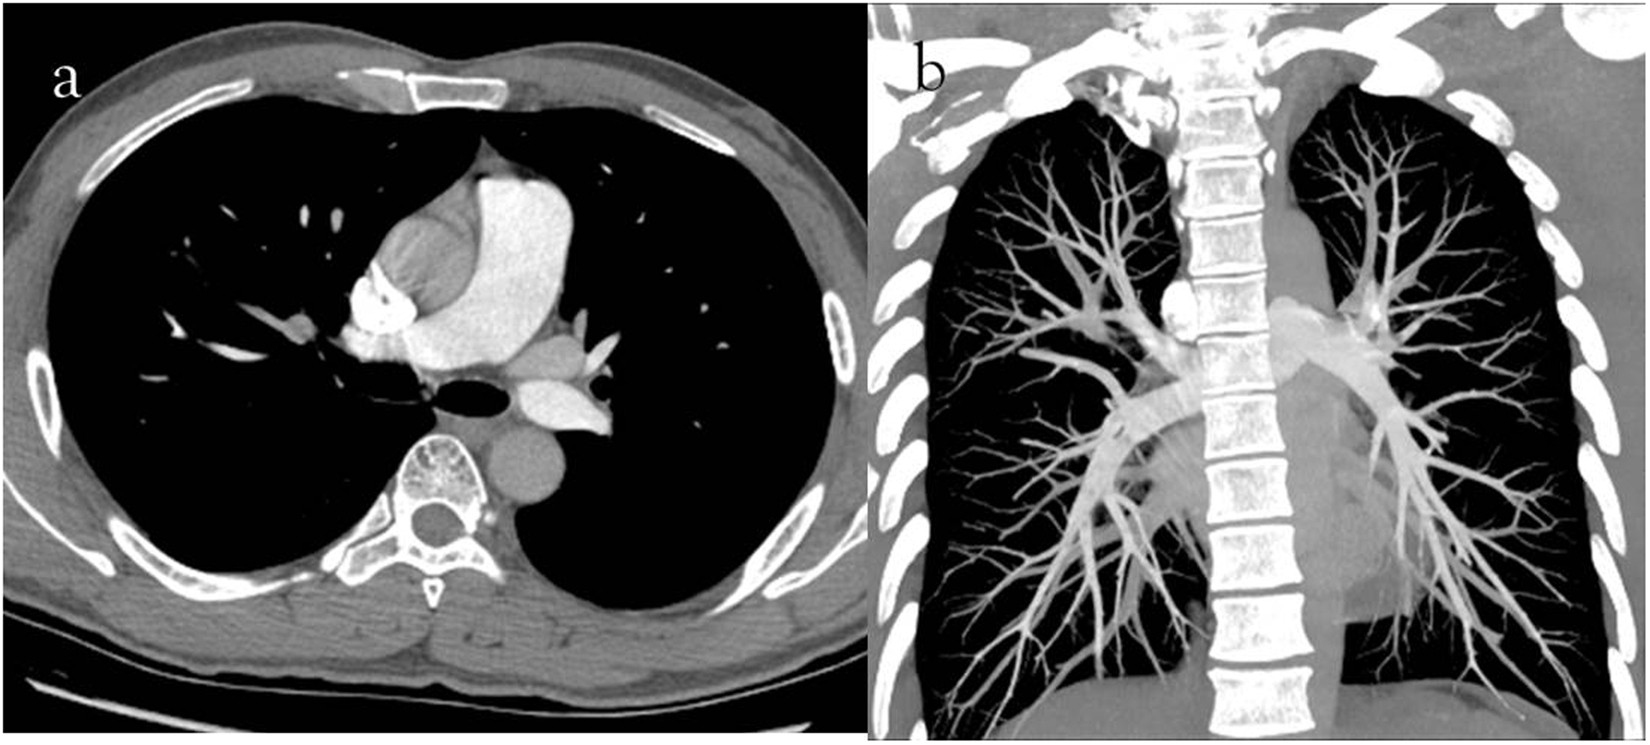

Figure 2

(a) 40-year-old man with pulmonary embolism. The CTPA performed with 120 kVp/40 ml 350 mg I/ml. Severe iodine contrast agent beam hardening artifacts in the superior vena cava (a, axial thin slice image) were observed, and 5–6 pulmonary arterial branches (b, coronal MIP image with 800 Hu-window width and 80 Hu-window center) were displayed.